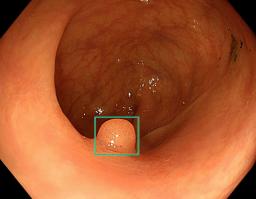

AIを使った大腸検査の補助システムの画面。ポリープと思われる部分を四角で囲って医師に示す(森悠一オスロ大教授提供)